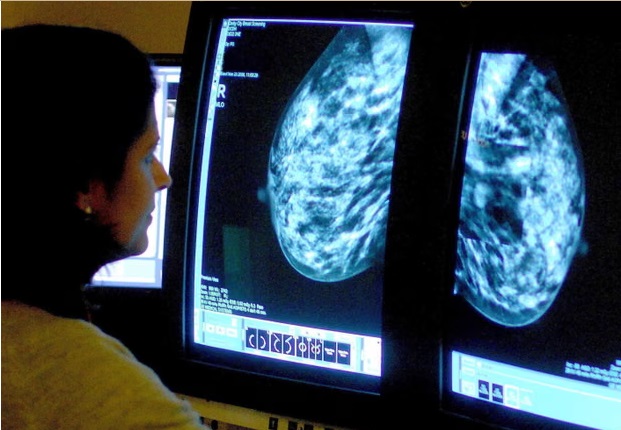

Cancer charities call for earlier diagnosis as cases projected to surge in England by 2040 theguardian.com

Cancer cases are projected to surge in England by 2040, with a person diagnosed every two minutes, up from one every four minutes in the 1970s. More than 6 million new cases of the disease are predicted to be diagnosed over the next 15 years, with the NHS at risk of being unable to cope unless action is taken to prevent more cases and diagnose the disease earlier, when it is more treatable.